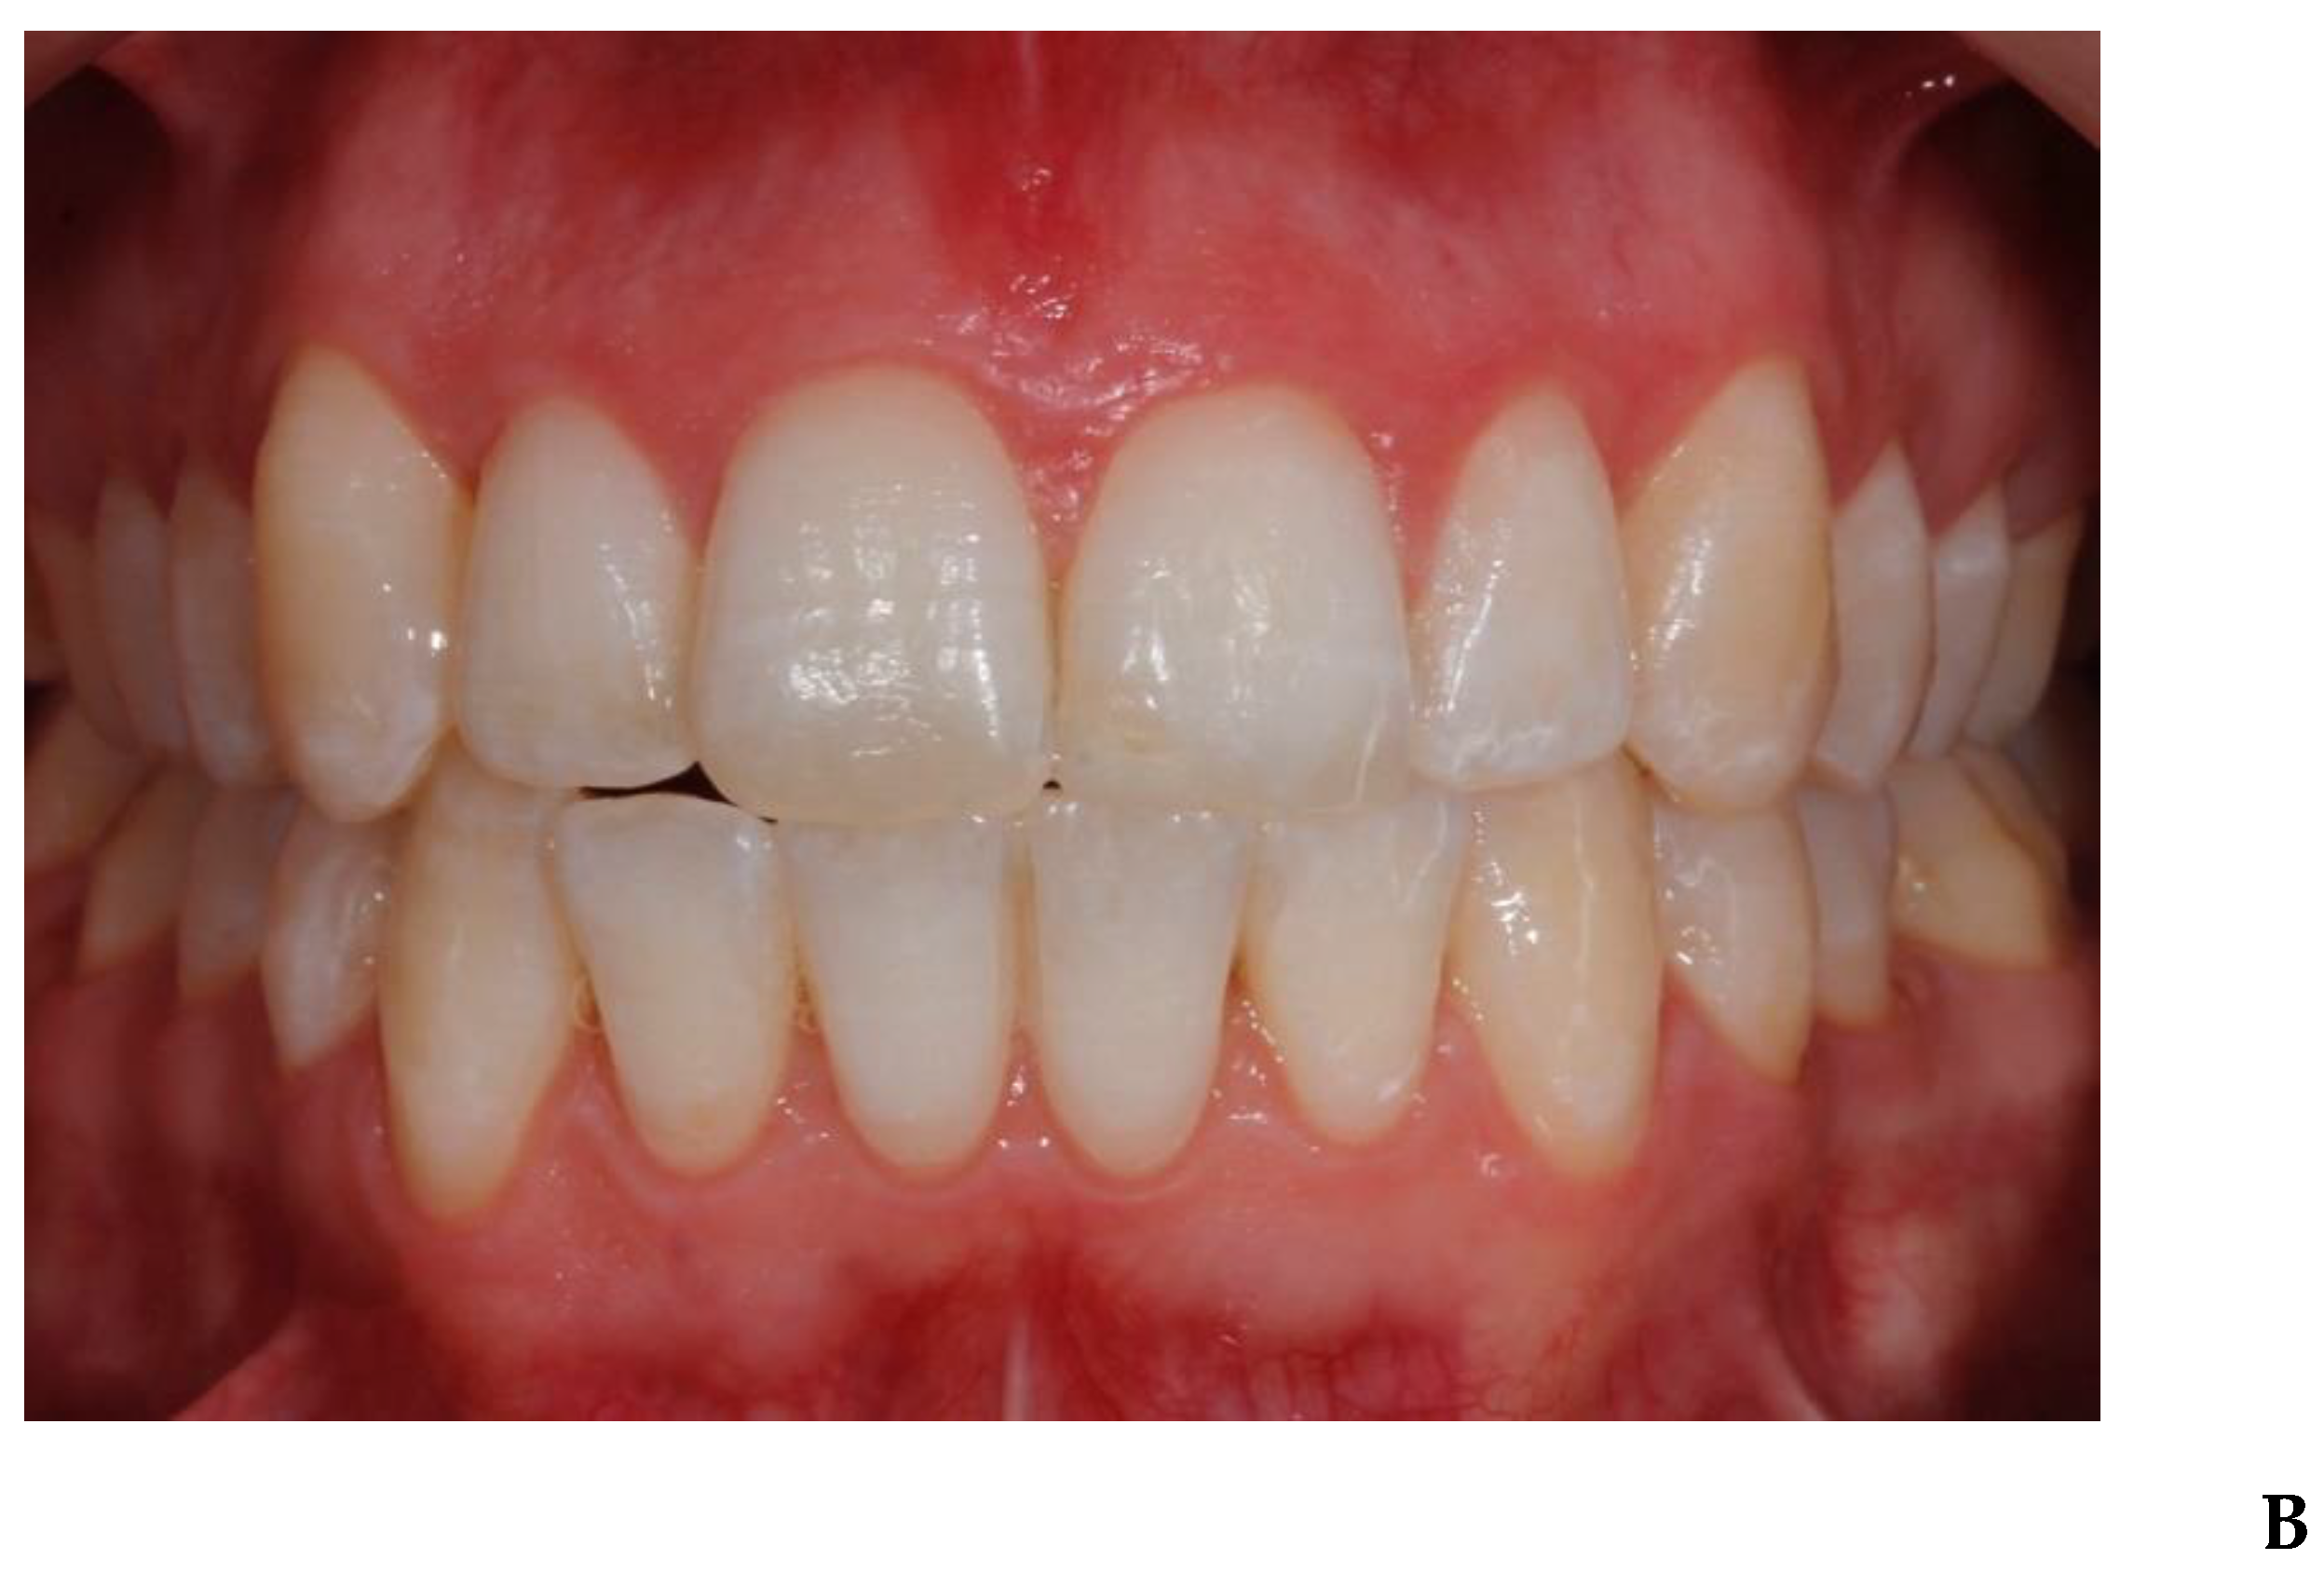

3. Results